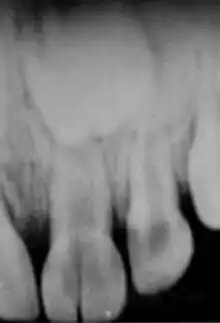

Intrusion

II s'agit du déplacement de la dent dans son alvéole souvent accompagné de fracture alvéolaire. Signes cliniques : la dent est plus courte voire invisible (attention que la dent soit toujours là), il y a une douleur spontanée et un son métallique à la percussion de la dent.